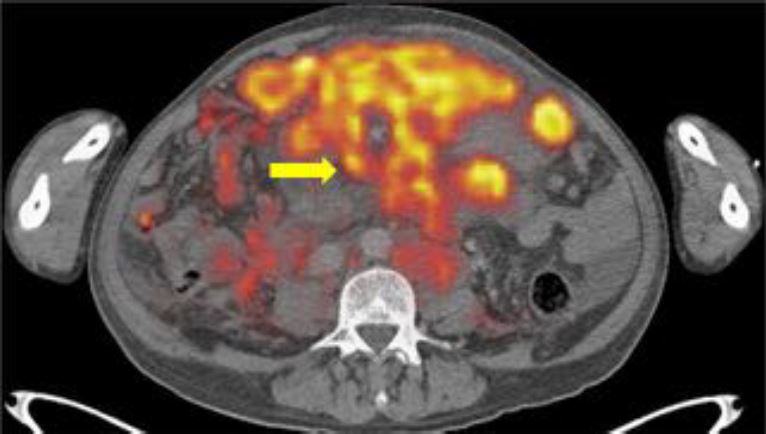

La carcinomatosis peritoneal (CP) se define como la diseminación o extensión de un cáncer originado en algún órgano o víscera del abdomen a la cavidad peritoneal. Independientemente del origen, indica siempre un estadío avanzado de la enfermedad neoplásica de base, con muy mal pronóstico.